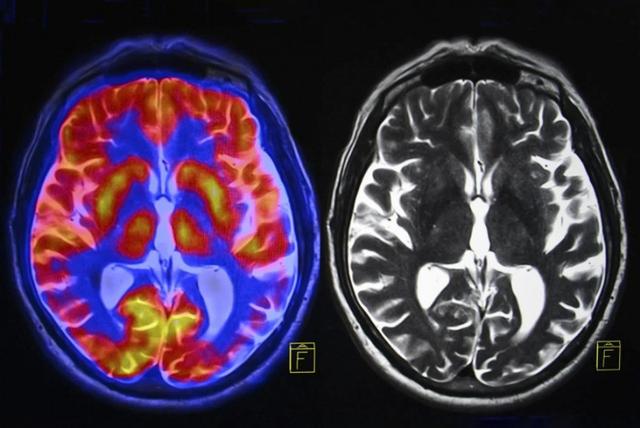

课题组分别招募了29名专业观鸟者和新手爱好者,对他们的大脑皮质层做磁共振检查。

结果表明,专业观鸟者大脑中与注意力、感知力相关的区域,结构更紧密、更复杂,且这种差异与鸟类识别能力直接相关。

专家解释,观鸟不仅需要敏锐的视觉,更依赖良好的记忆力与长时间专注力,这些行为会持续刺激大脑神经。相比音乐、阅读等静态健脑方式,观鸟所处环境多变、不确定性更强,对感知、专注与记忆的要求更高,能更持续地激活大脑。

进一步测试还发现,老年专业观鸟者的面部识别能力,显著优于同年龄段新手,这也印证了大脑结构的改变,确实能提升日常记忆与认知水平。